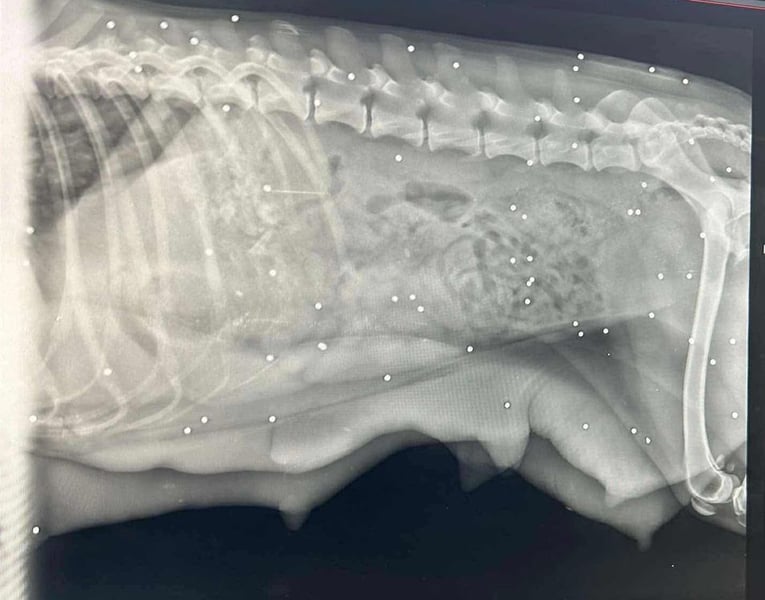

Bemerkungen: Auf die Hündin wurde wohl geschossen. Sie ist geröngt, allerdings steht das medizinische Gutachten noch aus.